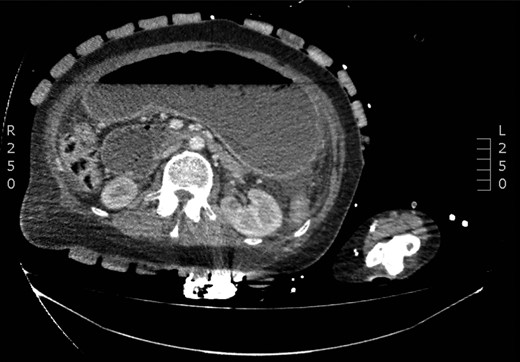

The patient was admitted as an emergency with abdominal pain and vomiting, following an episode of binge eating. A CT scan showed a grossly dilated stomach and a small volume of free gas in the abdomen (Fig. 1). Diagnostic laparoscopy did not reveal a perforation. His condition improved with antibiotics and decompression of the stomach with an NG tube. He was discharged after a 9-day admission.